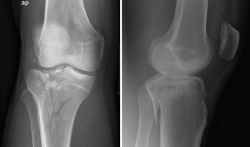

3. Artrosis

La gonartrosis es la causa más frecuente del dolor de rodilla después de los 50 años. En la radiografía se observa una reducción de la interlínea femorotibial o femoropatelar, y una osteofitosis marginal (Figura 6).

Figura 6. Radiografías anteroposterior y lateral de rodilla: osteofitos en compartimentos femorotibial y femoropatelar.